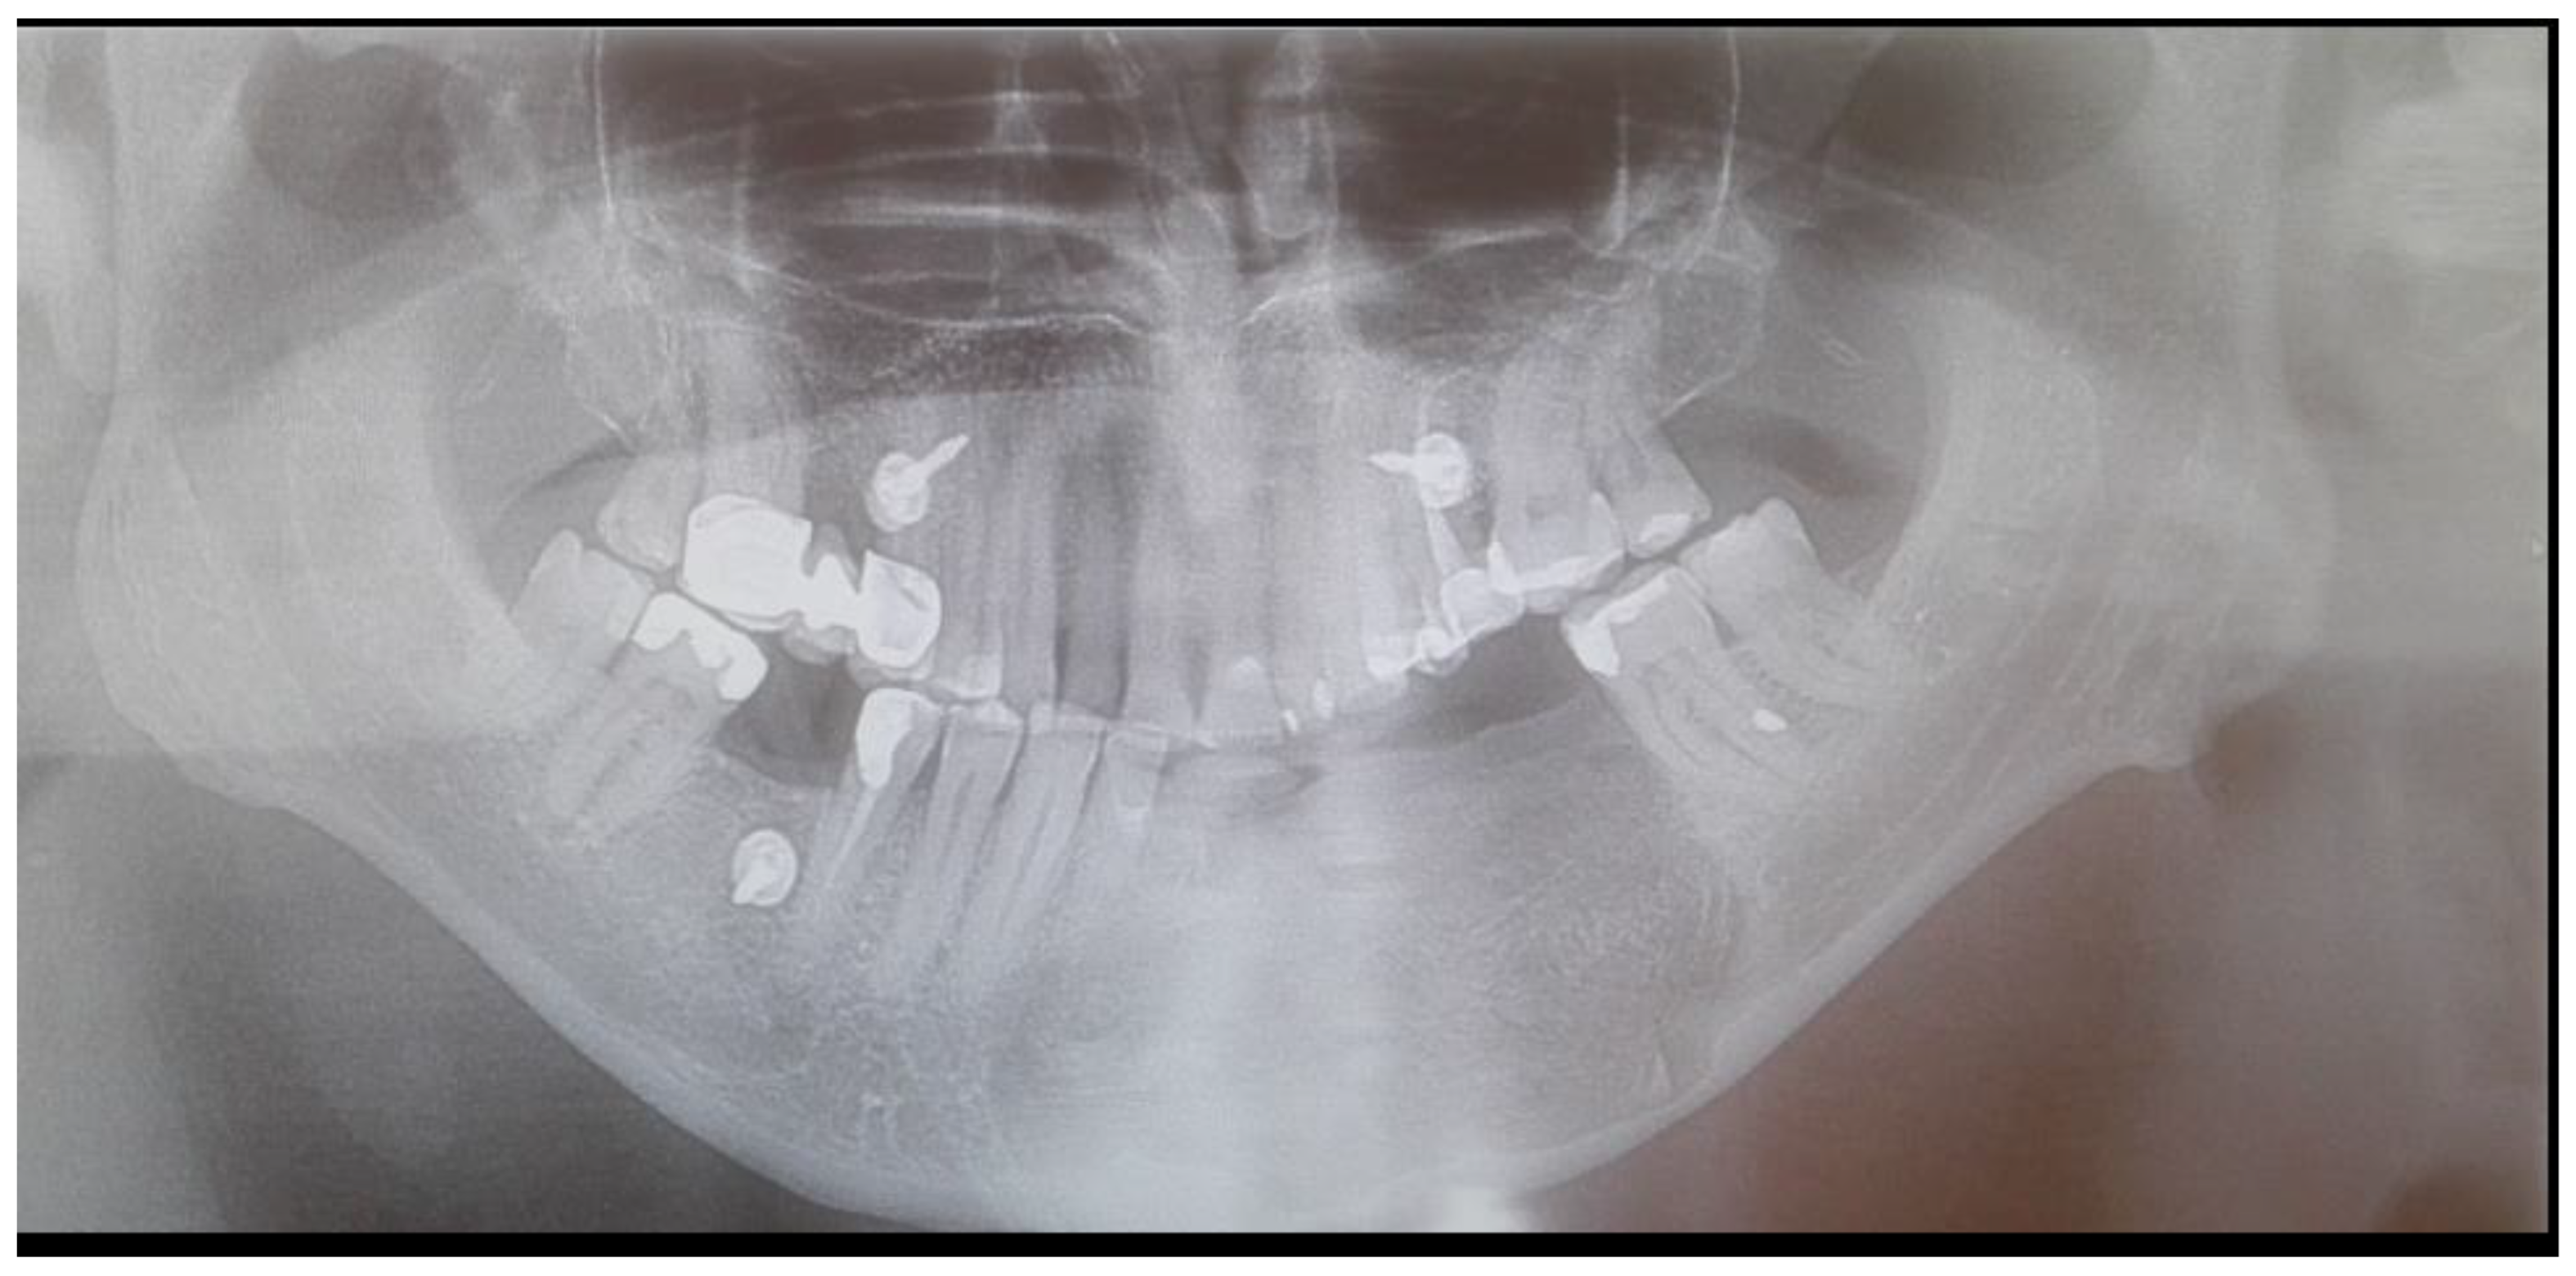

The final HP examination revealed the presence of OKC. During routine check-ups the healing was good, the swelling was normal, and sutures were removed after 14 days. The follow-up examination was made four years after surgery. During the consultation, the clinical and radiological appearance of the bone and surrounding soft tissue was normal. Proper bone healing was achieved clinically and on routine CBCT (Figure 7, Figure 8 and Figure 9). Four dental implants, Neodent 3.5/8 mm and 4.0/10 mm (Straumann Group, Arlington, TX, USA), were scheduled. The patient was supposed to be scheduled for FMT (full mouth therapy) and dental implant placement, however, because of the SARS-CoV-2 pandemic, the patient used partial acrylic removable dentures for over two years. By that time, the patient got used to the dentures and decided to reject the proposed further implant placement (Figure 10, Figure 11 and Figure 12).

Figure 6. Postoperative radiograph after 8 days from surgery. The loss of left mandibular IMF screw is visible. A noticeable high vertical diameter of bone is visible.